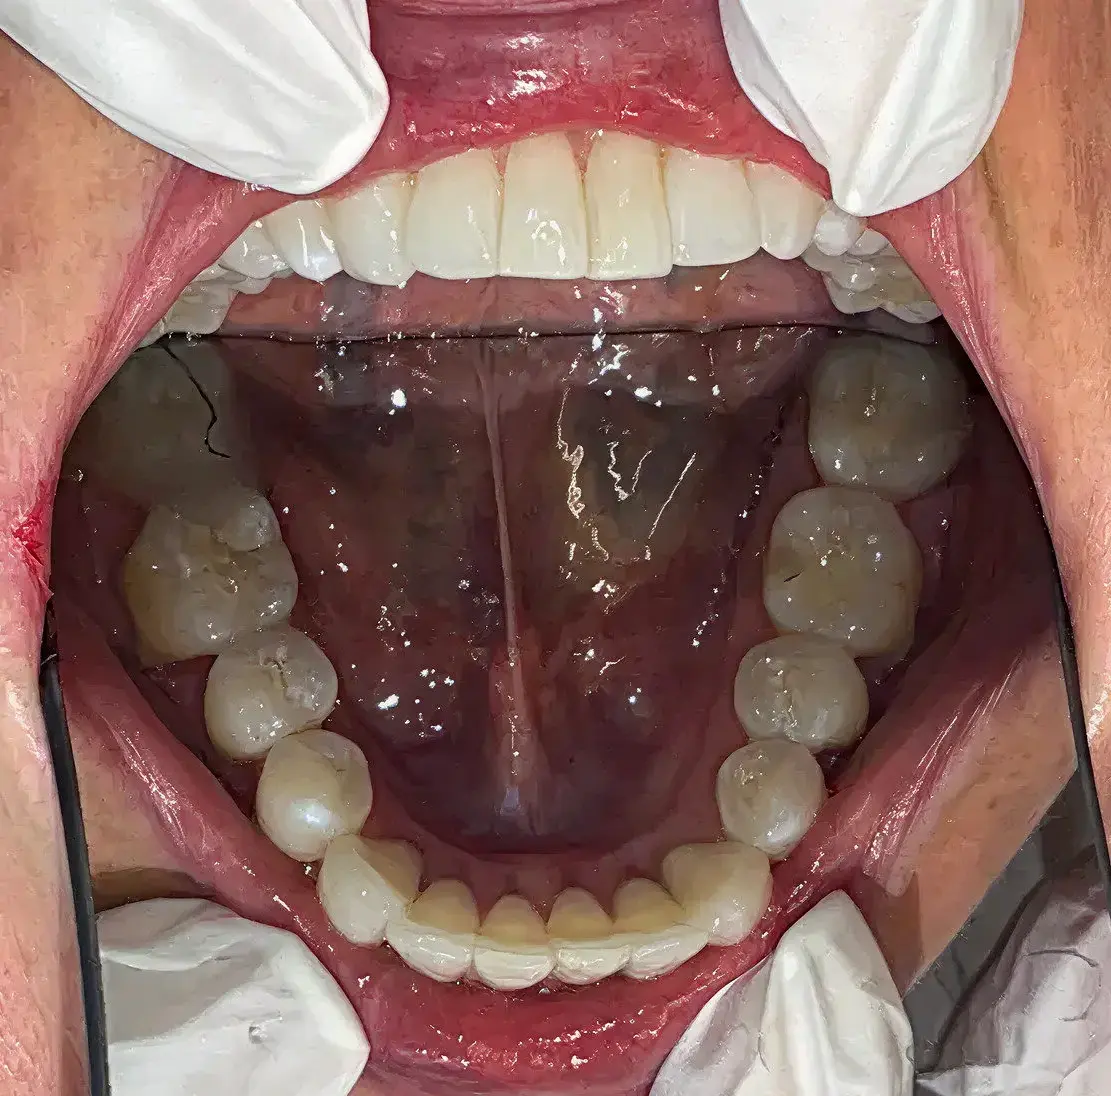

Vi tilbyder alle former for tandbehandlinger med speciale i både funktionelle og æstetiske løsninger som snorkeskinner, tandretning med Invisalign samt professionel udført tandblegning.

En tandlæge med høj faglighed sikrer, at behandlingerne udføres korrekt og holdbart, mens fokus på æstetik sikrer, at dine tænder ser naturlige og harmoniske ud. Hos Tandlægerne Nørrebrogade tilbyder vi bl.a.: